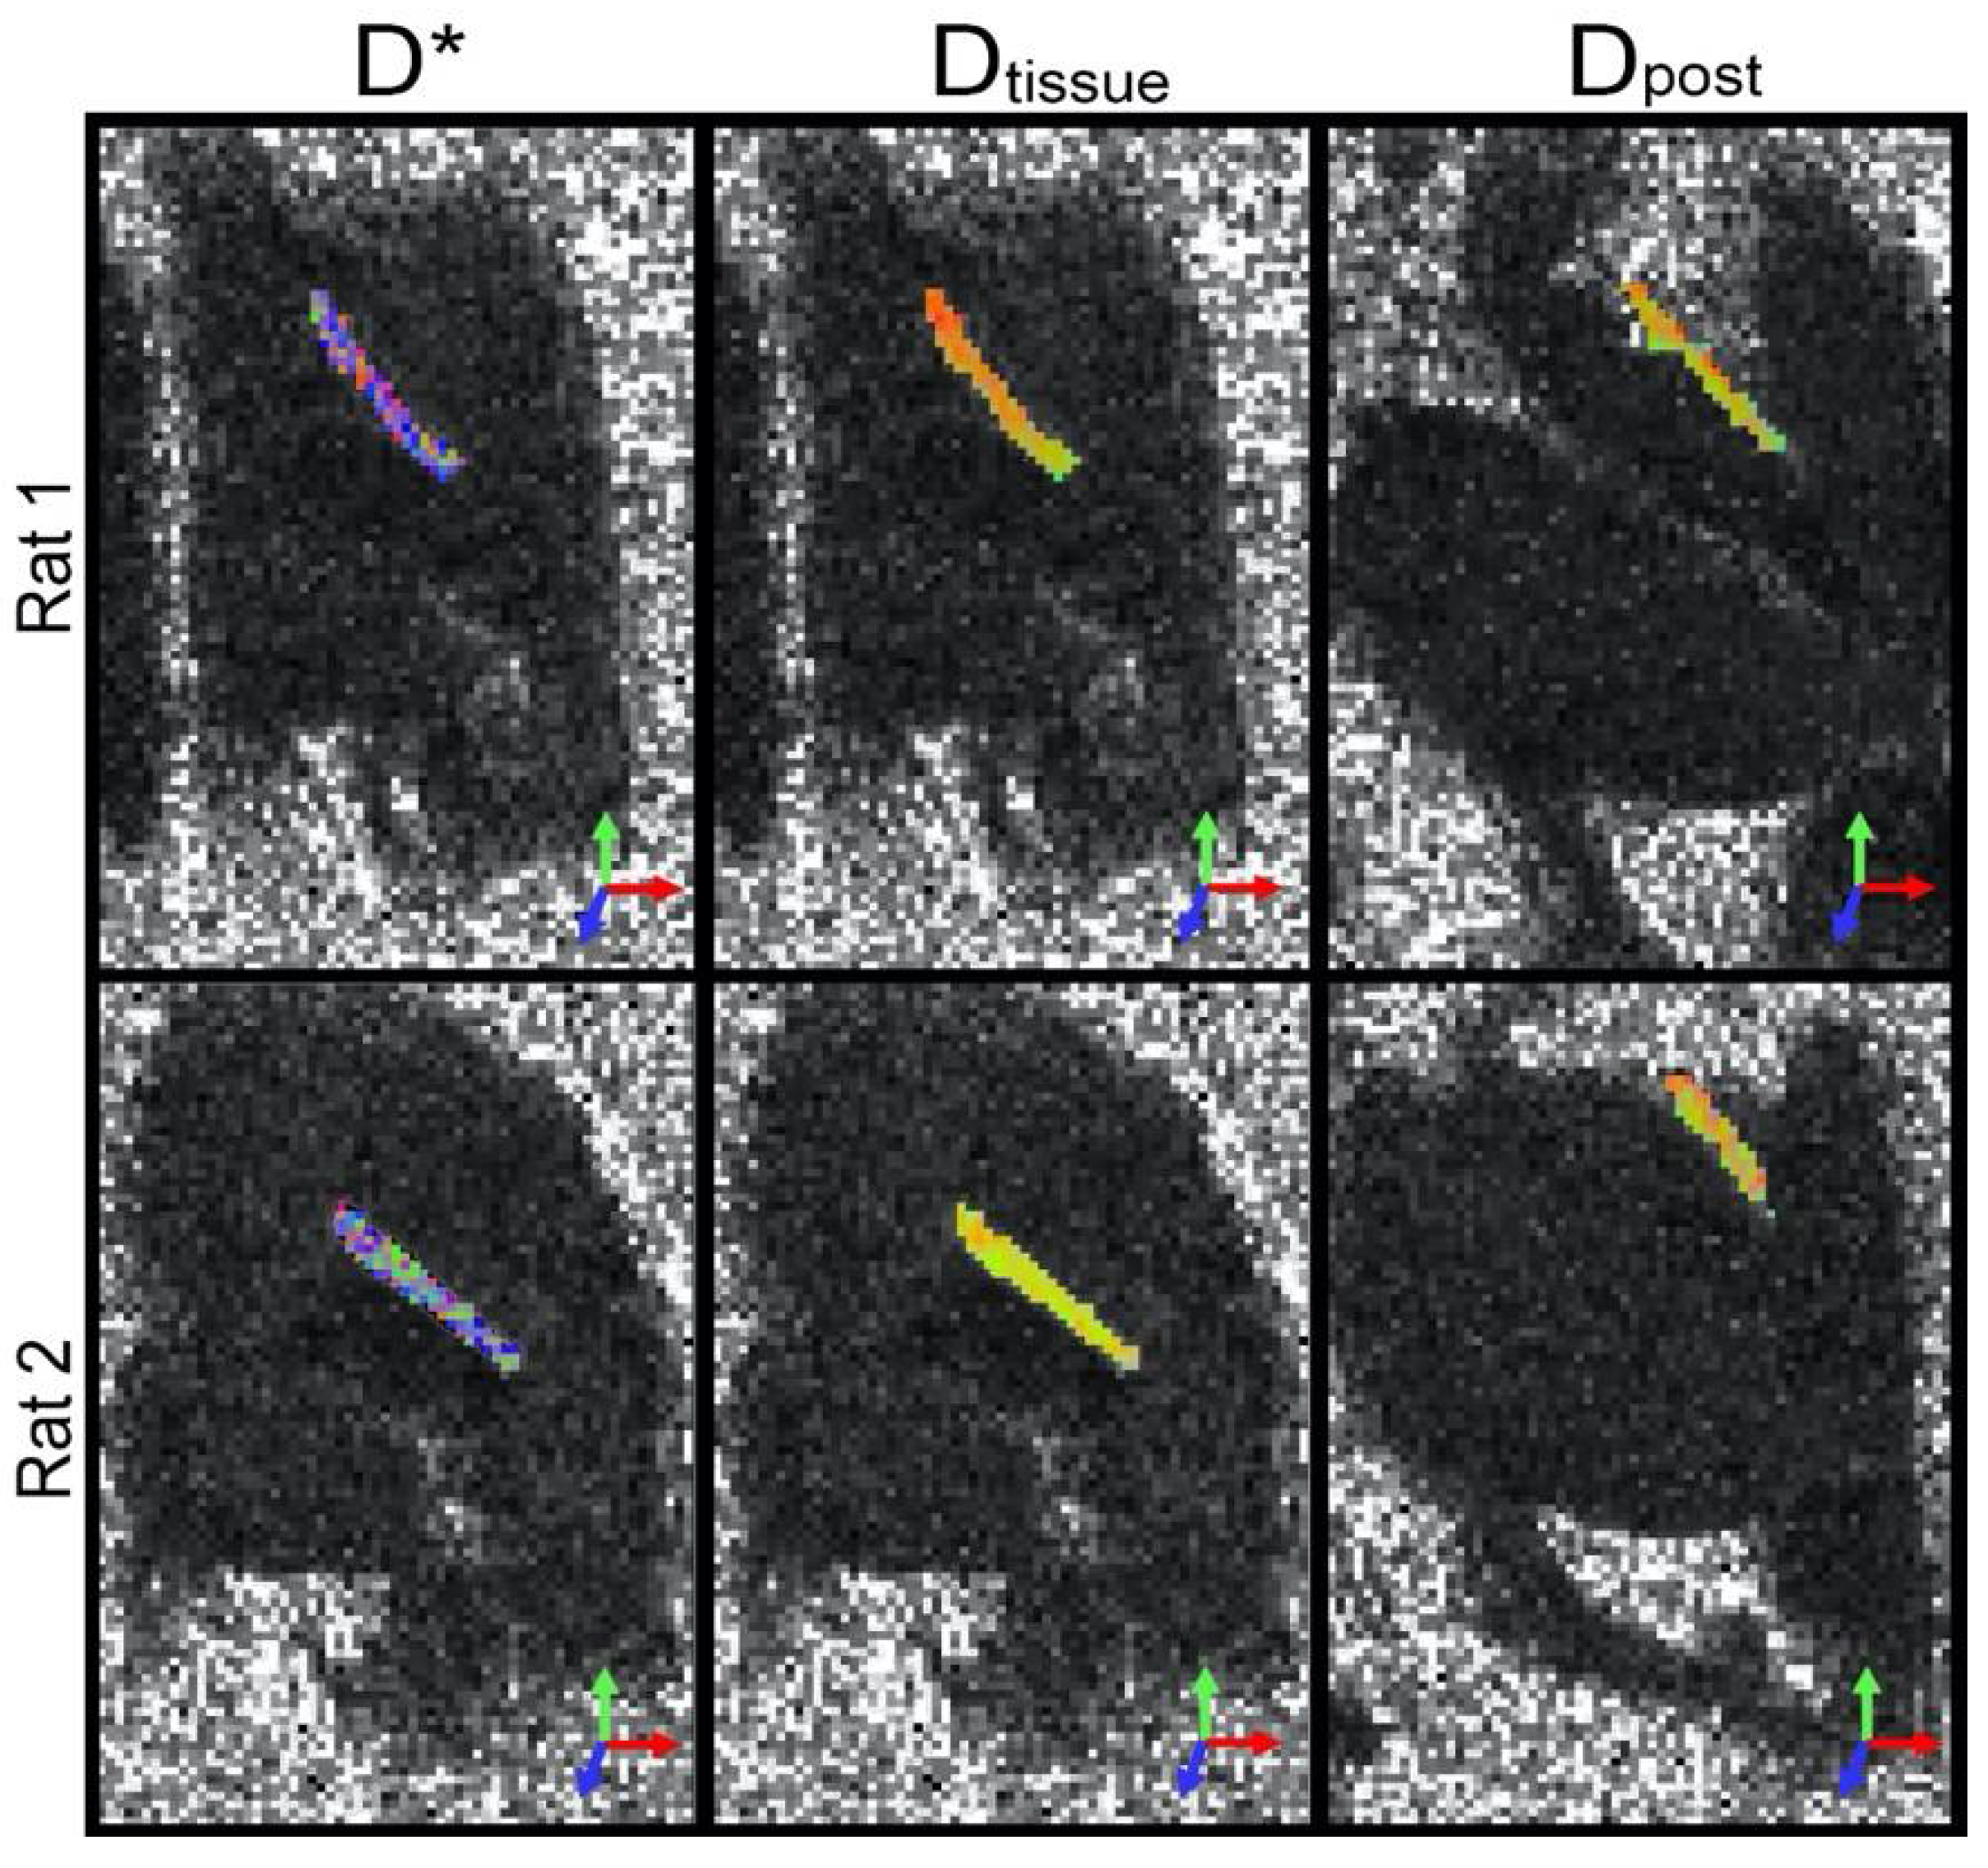

2.2. Data Analysis

3. Results